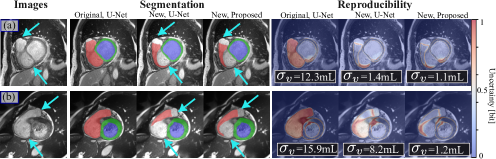

Refer to caption

Figure 4: Distribution of segmentation reproducibility as measured by volume standard deviation σvsubscript𝜎𝑣\sigma_{v}. Statistics (mean ± std) are given in corresponding colors.

Figure 5: Examples of RVOT segmentation and reproducibility. High uncertainty indicates strong disagreement among different ensemble models. (a) Models trained with the original labels are uncertain on basal slices with both the valve and atria (cyan arrows) inplane. (b) The reproducibility is largely improved by the new annotations, and further reduced by the proposed method.

All methods have a volume variance that peaked at a relatively low value (<5absent5<5 ml), especially at ES. However, we observe that the U-Nets trained with the original annotations have a longer tail than networks trained with the new annotations. The proposed method exhibits the highest reproducibility with a sharp peak. Fig. 5 (a) is a basal slice that covers the partial atrium and valve (cyan arrows) on the image plane. In this slice, we observe that the networks trained with the original annotations are highly uncertain, resulting in a volume SD of 12.312.312.3 ml. In contrast, the networks trained with the new annotations successfully delineate the RVOT and have a reduced SD of 1.11.4similar-to1.11.41.1\sim 1.4 mL. In Fig. 5 (b), we show a case in which the vanilla U-Nets can have low reproducibility because the RVOT and atrium are not distinguishable, with σv=8.2subscript𝜎𝑣8.2\sigma_{v}=8.2 mL. In comparison, our proposed method reduces σvsubscript𝜎𝑣\sigma_{v} to 1.21.21.2 mL. The results suggest that consistent annotation and loss-of-tracking can greatly improve reproducibility when segmenting difficult regions like the RV base.